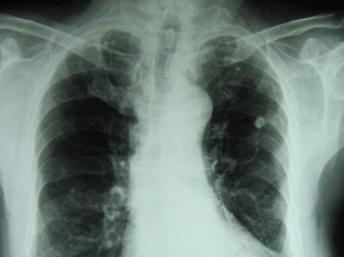

Lây nhiễm đến gần 10 triệu người và khiến gần 1,5 triệu người chết trên thế giới hàng năm, bệnh lao vẫn là một trong các căn bệnh đáng sợ đối với nhân loại. (DR)

Việc xuất hiện các loại vi trùng lao kháng thuốc và t́nh trạng điều trị yếu kém tại nhiều khu vực và quốc gia khiến lao tiếp tục là một trong những bệnh truyền nhiễm gây tử vong hàng đầu trên thế giới, với gần 1,5 triệu người/năm. Riêng ở Việt Nam, theo một số liệu thống kê trong nước, mỗi năm có khoảng gần 200.000 người mắc lao, trong đó có khoảng 5.000 đến 6.000 người bị vi trùng lao kháng thuốc, và gần 30.000 người chết do bệnh lao nói chung.

Bác sĩ Đinh Xuân Anh Tuấn lưu ư bệnh lao là một trong các bệnh thông thường nhất. Theo một số thống kê gần đây của Liên Hiệp Quốc, 1/3 nhân loại đang hoặc đă bị nhiễm vi trùng lao. Lao là loại vi trùng rất dễ lây lan. Dù bệnh lao không c̣n gây tử vong ở mức độ rất cao như xưa nữa, nhưng vẫn c̣n là nguyên nhân tử vong lớn.